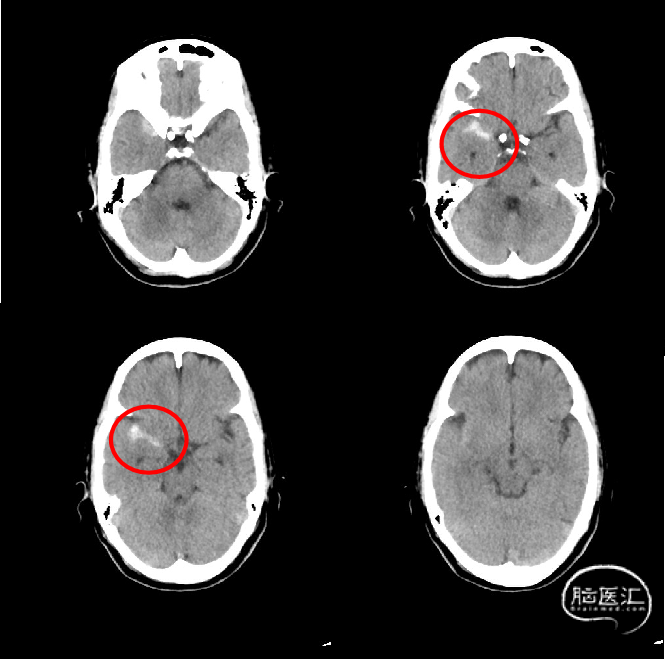

15:10 停用替罗非班,急查头颅CT。

少量出血(SAH?实质?),无神经功能受损。

D0 2022-2-21

D1

D3

D7